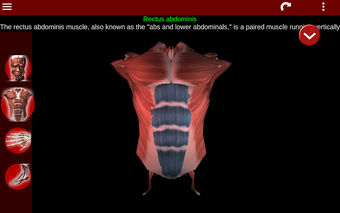

Esta herramienta educativa proporciona una descripción de cada músculo del cuerpo humano, así como un modelo tridimensional del sistema muscular. Con sólo tocar con el dedo, la aplicación revelará la información pertinente.

Los usuarios pueden hacer zoom sobre el músculo, así como elegir si ocultar o mostrar los datos. La orientación puede ser horizontal o vertical, según convenga más.